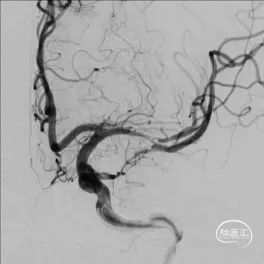

术后影像及检查

全脑及病变处不同体位造影:狭窄处成形好,未残余明显狭窄,左大脑中动脉主干及各分支显影好。

术中将Navien导管送至颈内动脉岩骨段,增加支撑力,将两条微导丝分别送入左大脑中动脉上下干,先沿上干微导丝送入球囊扩张,效果差, 再沿下干微导丝送入球囊扩张,效果仍差,大脑中动脉M1末端狭窄有改善,但狭窄仍较重,遂用赛诺神畅 颅内药物支架NOVA DES®2.25*10mm置入左大脑中动脉M1末端及上干内,球囊扩张成形,支架成形好,血管成形满意,确定下干无闭塞后,撤出下干微导丝。